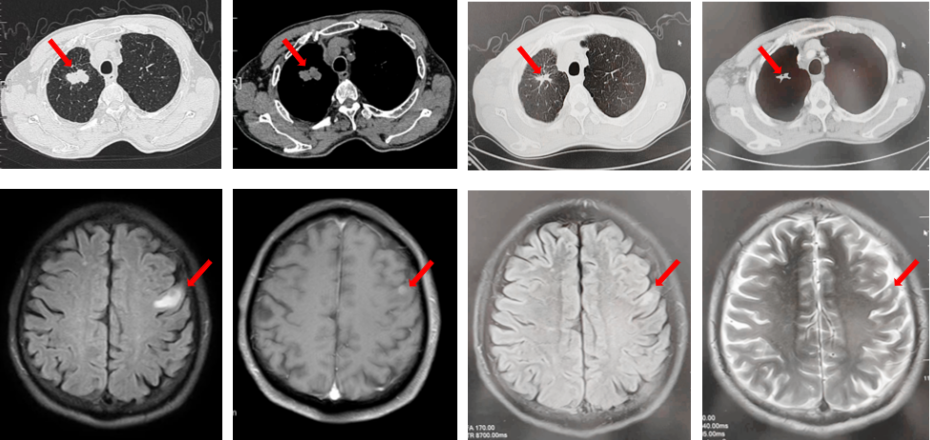

67岁女性患者,无既往病史。2019年10月患者因右侧季肋部不适行肺CT提示右肺中叶改变,双肺结节,右侧胸腔积液。行右侧胸腔穿刺引流,送检胸腔积液,液基薄层结果提示肺腺癌。确诊为右肺中叶恶性肿瘤cT2bN1M1a IVA期。基因检测(胸腔积液):EGFR L858R突变。建议患者口服奥希替尼,患者拒绝。2019年11月始口服埃克替尼,定期复查,最佳评效PR(图5)。

图5:A.第2例患者的基线影像资料,由上至下依次为右肺肿物、双肺转移灶及右侧胸腔积液;B.EGFR-TKI一线治疗后最佳复查评效,肺内病灶较前缩小,胸腔积液较前明显吸收。

2020年11月复查评效PD。复测基因检测(血检):T790M阳性,改行奥希替尼治疗,期间评效均为SD(图6)。

图6:A.埃克替尼靶向治疗后病情进展,肺内病灶较前增大,右肺近胸膜处新发转移灶;B.更换三代EGFR-TKI治疗后复查多处病灶未见明显变化。